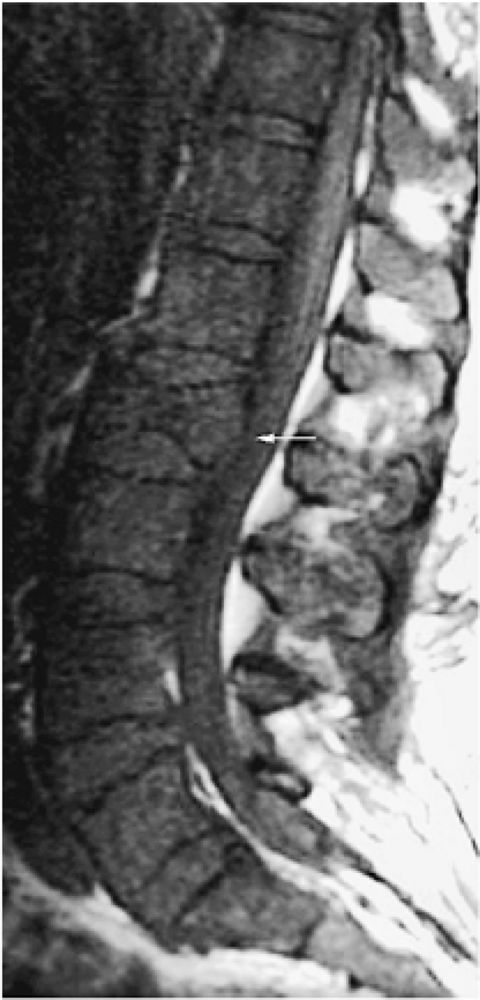

![]() |

FIGURE 13.48 ● A diffuse pattern of marrow replacement of the elbow is indicated in gray on this coronal graphic illustration.

FIGURE 13.49 ● Sagittal T1-weighted image shows a diffuse pattern of involvement of the thoracic spine. Myelomatous infiltration is hypointense. Multiple compression fractures are present (arrows).